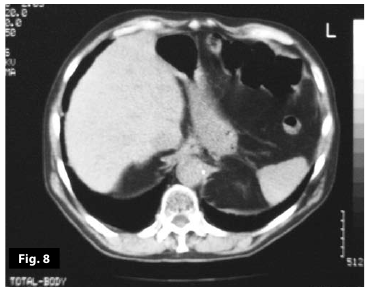

Figure8

Figure7-8